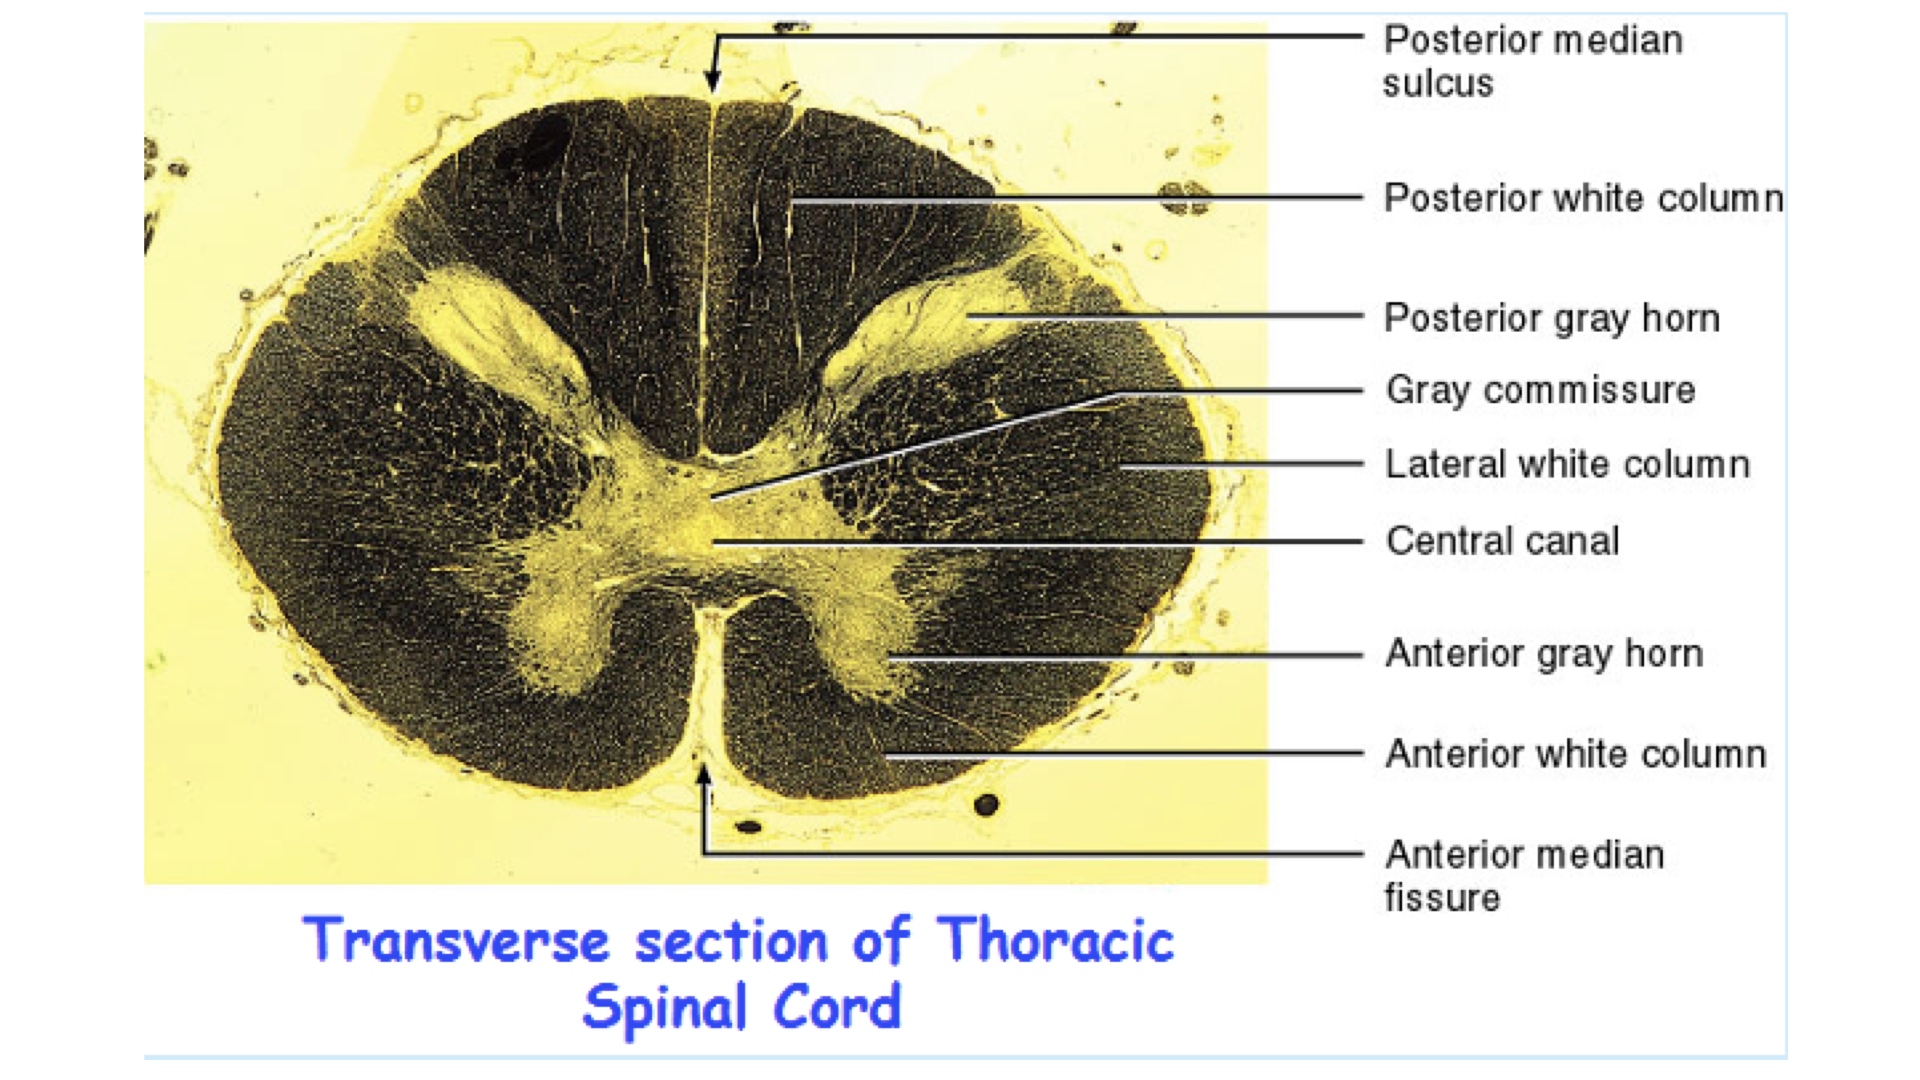

4. Composed of gray & white matter – histologically H shaped grey matter surrounded by white matter

a. Gray matter - unmyelinated tissue, mainly cell bodies, soma, nissl bodies

b. White matter - myelinated tissue, mainly axons

4. Anterior median fissure – deep groove along the ventral surface

5. posterior median sulcus – shallow groove on the dorsal surface

1. Gray matter

a. Composed of neuron cell bodies,shaped like an H or butterfly

b. Six projections called horns:

1. Two dorsal gray horns

2. Two ventral gray horns

3. Two lateral gray horns - found in thoracic lumbar

c. Transverse bar called the gray commissure

d. Central canal in center of gray commissures

2. White matter

1. Anterior median fissure

2. Posterior median sulcus